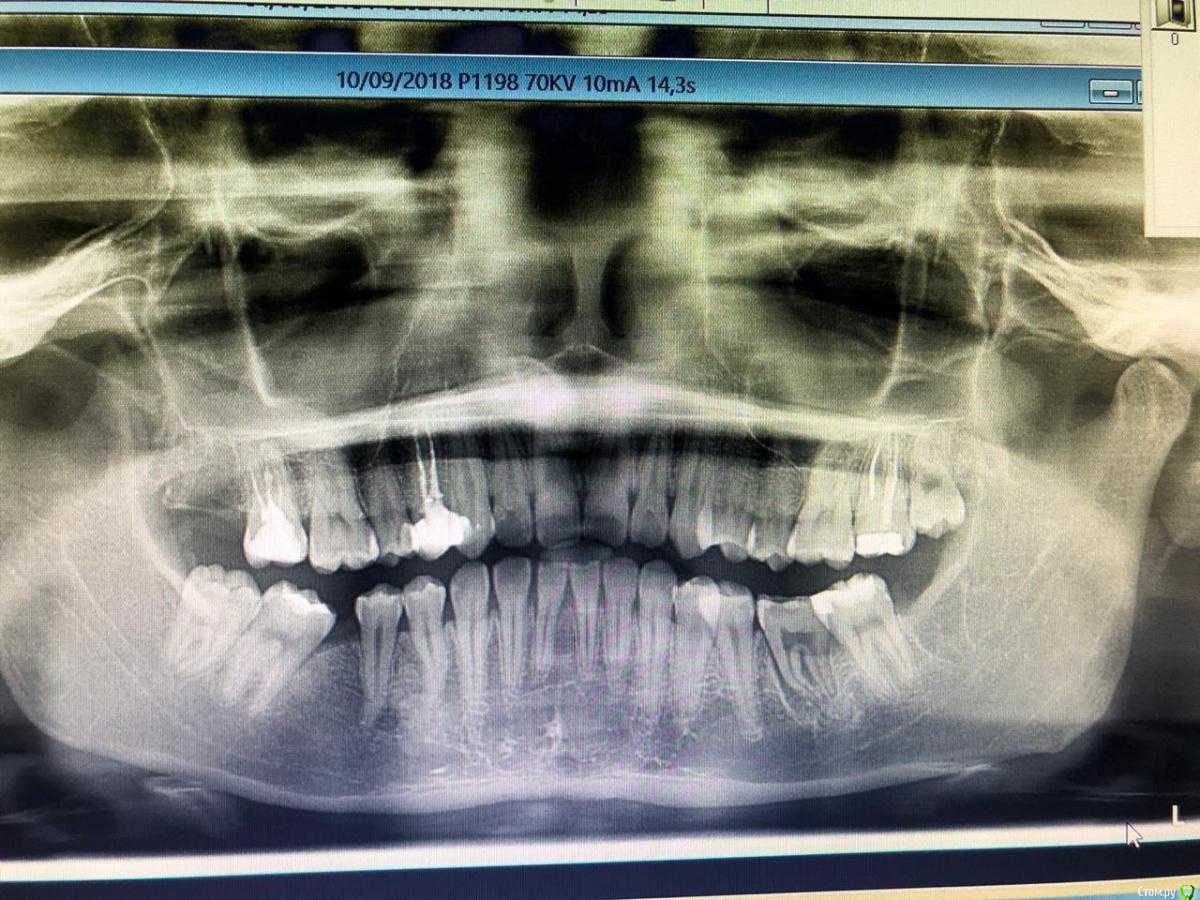

Daniyar Опубликовано 12 февраля, 2019 Поделиться Опубликовано 12 февраля, 2019 FYI 4 Ссылка на комментарий

Jurai Опубликовано 12 февраля, 2019 Поделиться Опубликовано 12 февраля, 2019 сколько времени прошло после вмешательства - на финальном снимке? Ссылка на комментарий

Daniyar Опубликовано 12 февраля, 2019 Поделиться Опубликовано 12 февраля, 2019 сколько времени прошло после вмешательства - на финальном снимке?09/02/19 Ссылка на комментарий